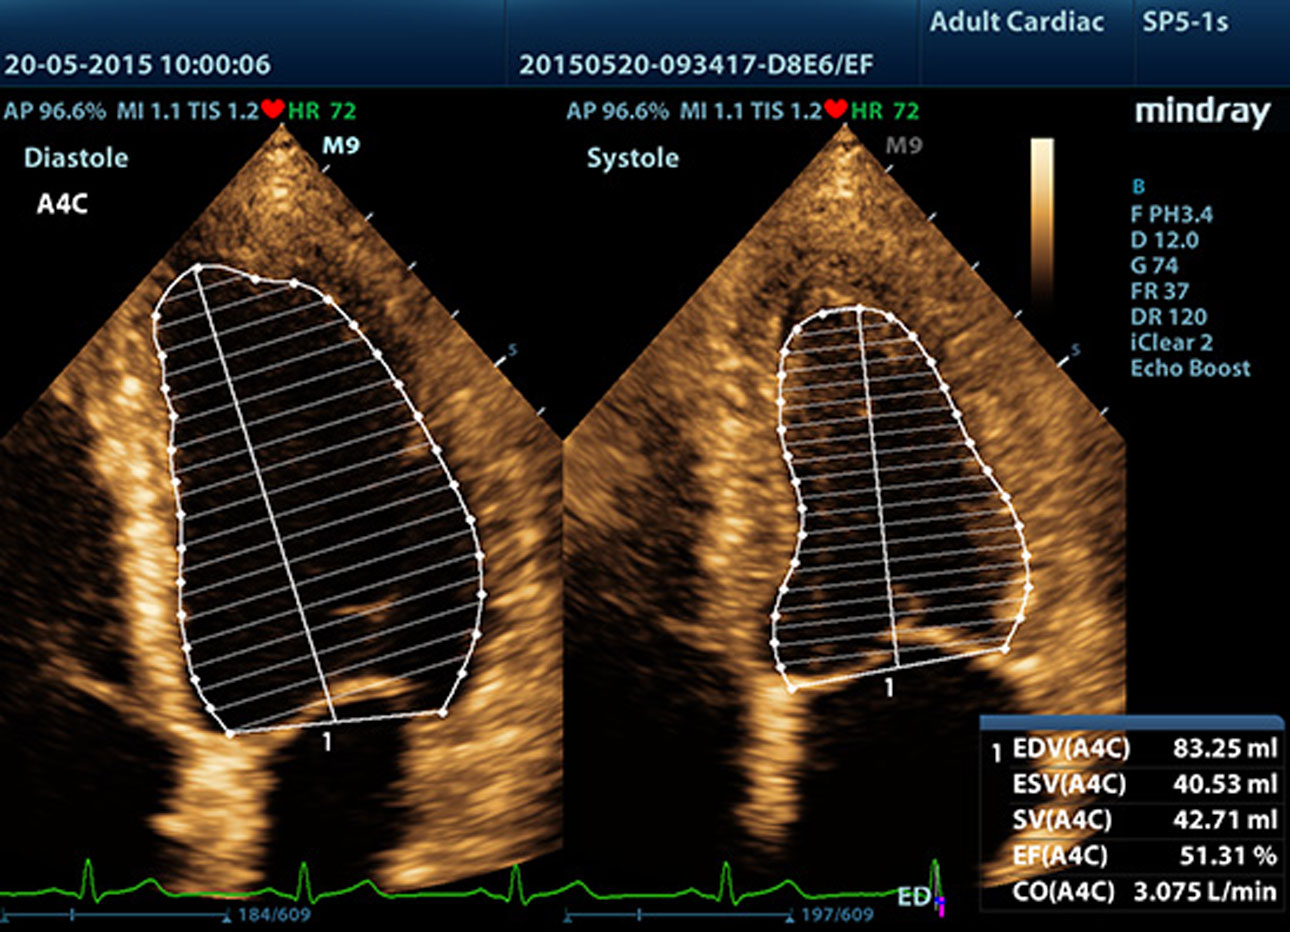

AutoEF

Een intelligente manier om 2D-echoclips zo te analyseren dat diastole/systoleframes automatisch worden herkend en EDV/ESV/EF-resultaten, enz. worden uitgevoerd via de Simpson-methode